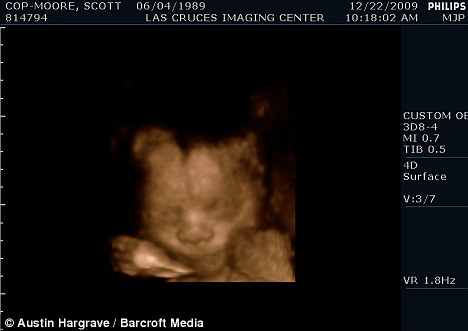

掃描顯示斯科特懷的是個(gè)男孩

現(xiàn)年30歲的斯科特·穆?tīng)柡驼煞蛲旭R斯來(lái)自美國(guó)加利福尼亞州,兩人原先都是女性,托馬斯接受過(guò)變性手術(shù)后成為真正的男子漢,斯科特仍然留有一些女性器官并持有女性出生證明,所以他們的婚姻是合法的。目前他們已經(jīng)知道未出生的孩子是個(gè)男孩,準(zhǔn)備給他取名“邁爾斯”。

2009年6月,斯科特從一名男性朋友那里取得精子,并通過(guò)人工受精成功懷孕。他打算在當(dāng)?shù)氐尼t(yī)院自然分娩。